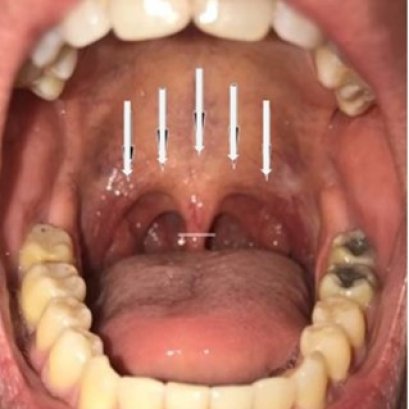

การใช้คลื่นความถี่วิทยุจี้เพดานอ่อน รักษานอนกรน

การร้อยไหมตกแต่งลิ้นไก่เพดานอ่อนและคอหอย แก้นอนกรน

การใช้คลื่นความถี่วิทยุหลายระดับ รักษานอนกรน